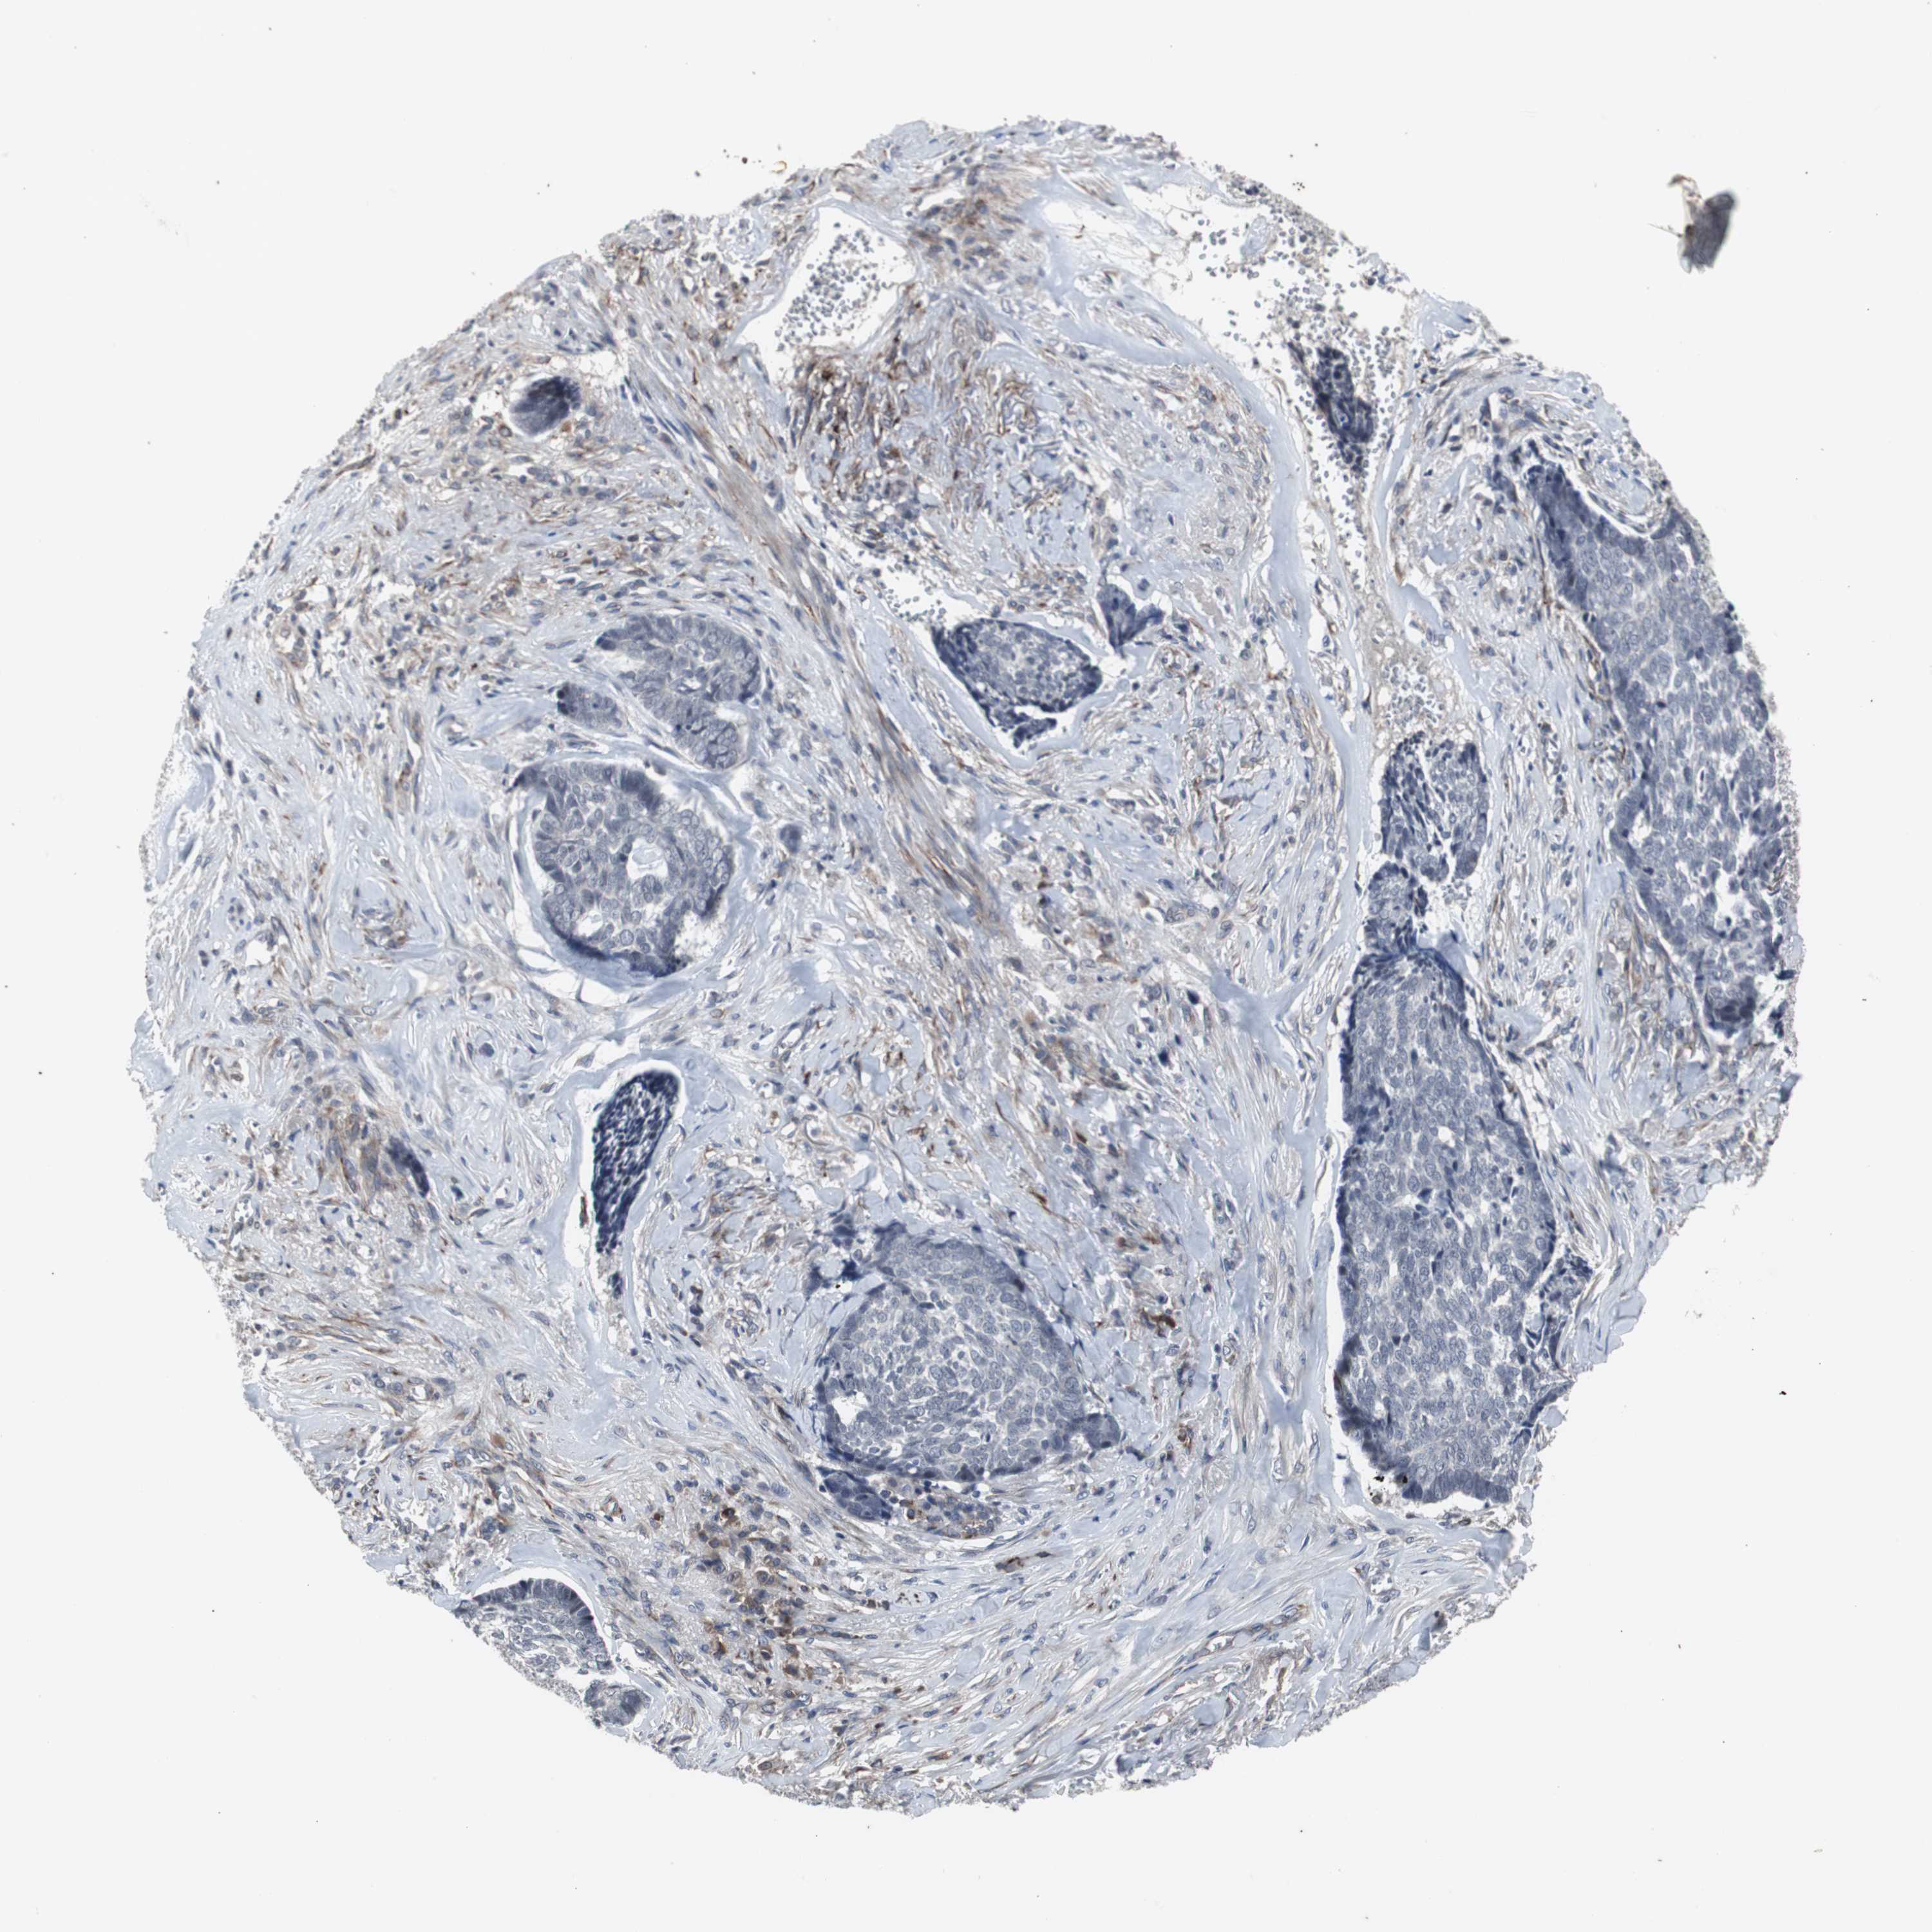

Antibody CAB005337

Staining

High

Medium

Low

Not detected

Intensity

Strong

Moderate

Weak

Negative

Quantity

>75%

75%-25%

<25%

None

Location

Nuclear

Cytoplasmic/membranous

Cytoplasmic/membranous,nuclear

Squamous cell carcinoma, NOS

Squamous cell carcinoma, metastatic, NOS

Basal cell carcinoma

Papilloma, NOS